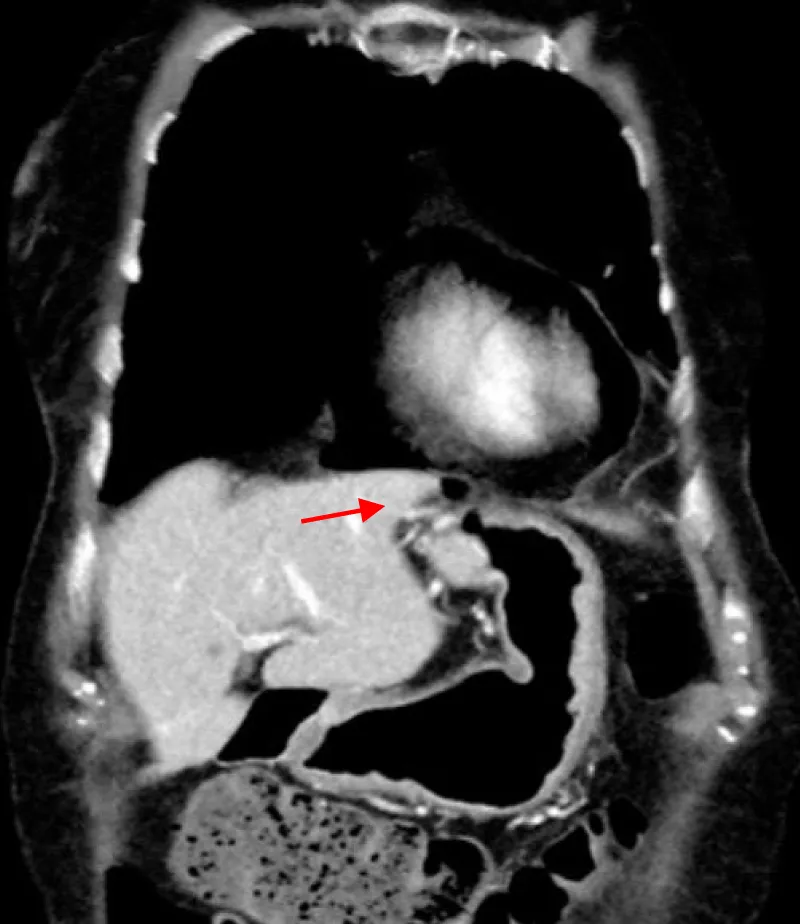

The approval of the hospital’s ethics committee was obtained to present the following case. A 78-year-old female patient was admitted to our hospital with complaints of recurring epigastric pain and diarrhea. The clinical workup revealed collagenous colitis. Upper GI endoscopy was normal. Her medical history included gastroesophageal reflux treated by Nissen fundoplication in 1980 with redo surgery in 2010. While hospitalized, she presented acute retrosternal and epigastric pain not responding to usual medication. Clinical evaluation revealed hemodynamic stability, pericardial metallic tinkling friction rub, mill wheel murmur, and no signs of peritonism. Blood analysis showed a slight inflammation while high-sensitive troponin dosage and leukocytosis were within normal range. Radiologic evaluation by CT scan revealed pneumopericardium associated with a fistula path going from the Nissen’s fundoplication valve towards the pericardial cavity (Figures 1,2).

Figure 1: CT scan showing fistula’s path (red arrow)./p>

Figure 2: CT scan showing pneumopericardium (red arrow) and pathologically edematous Nissen’s valve (green arrow).